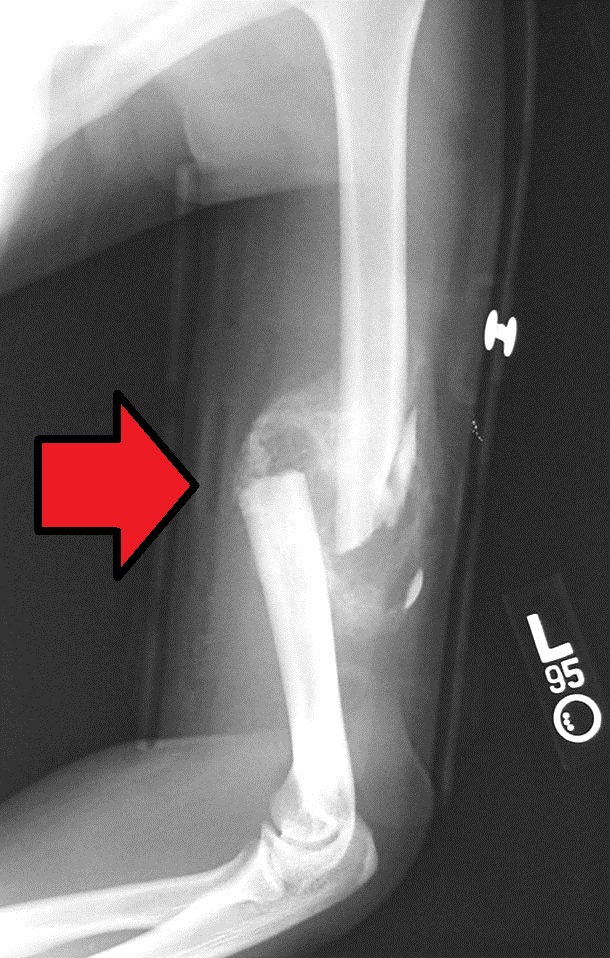

About 4 weeks after the fracture injury, in most normal healing individuals, bone callus formation will start to happen. You can see this by the formation of bone and cartilage that form around the fracture site, and it's main function is to stabilize the fracture site. That's the external callus.